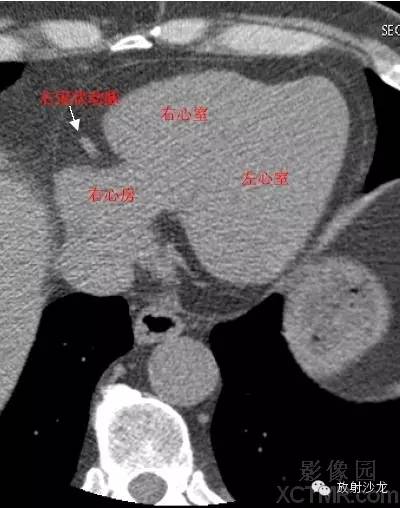

RA -Right Atrium右心房

RV -Right Ventricle右心室

LV -Left Ventricle左心室

RAA –Right AtrialAppendage右心耳